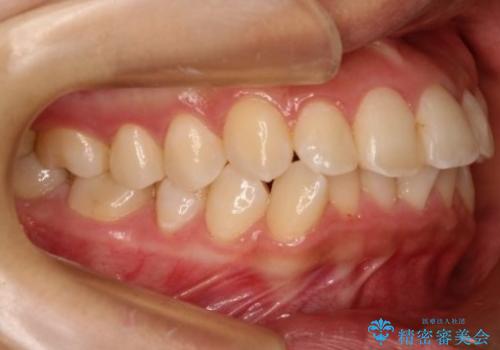

【非抜歯矯正】できる限り前歯を引っ込めたい

- 前歯の凸凹を主訴に来院されました。

非抜歯の範囲でできるだけ前歯を下げることを希望されたため、IPRと臼歯部の遠心移動を行い治療を行いました。当初はインビザラインで治療を行っておりましたが、使用時間を十分に確保できないことで途中からワイヤーを使用しております。